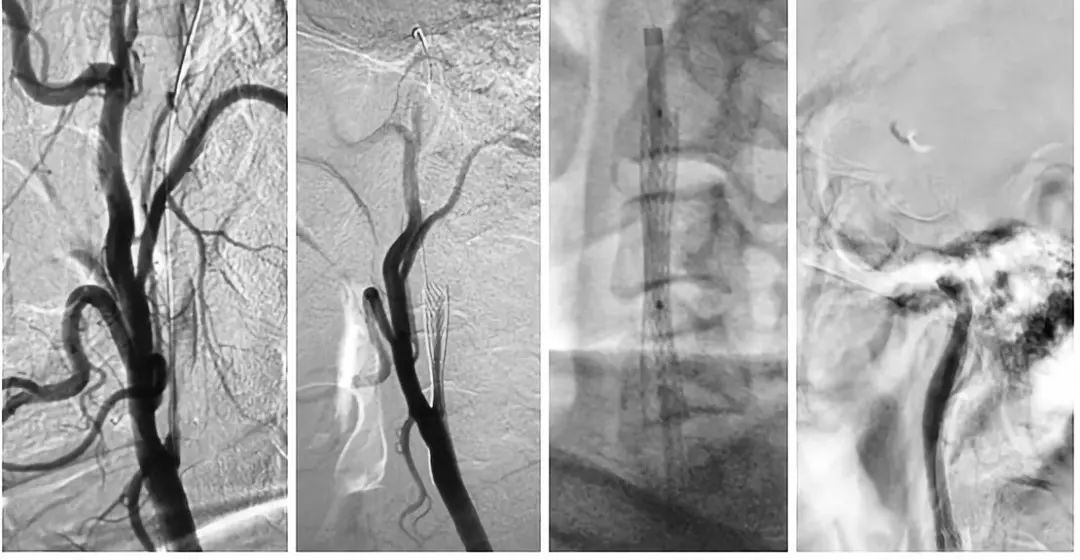

DSA结果提示:左侧颈内动脉次全闭塞,远端未见显影,左侧大脑中动脉闭塞,前交通动脉开放,左侧椎动脉起始部重度狭窄(图3-5)。

图3

图4

图5